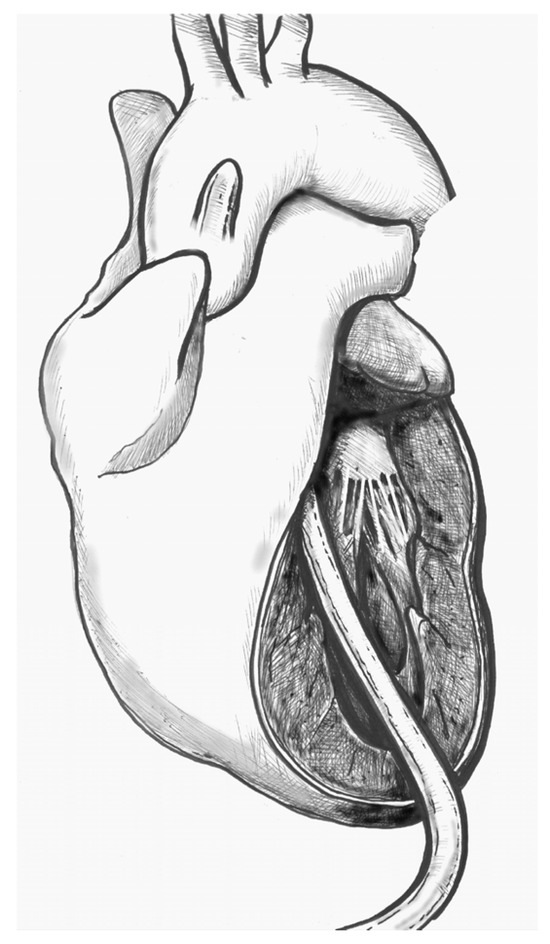

Background: Since the study of Lev and Thaemert in 1973, little has been published concerning the overall arrangement of the murine conduction tissues, in particular with relation to gross anatomical landmarks. We recently emphasised the potential va...